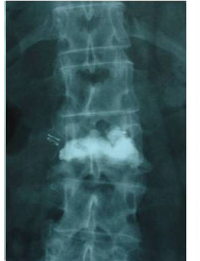

Cas clínic d'una resecció (corpectomia) i reconstrucció vertebral lumbar en una fractura esclat de nivell L4.

En els casos de les fractures més greus, com les fractures conminutes i les fractures d’esclat, un fragment del cos vertebral pot ficar-se dins del canal medular, provocant una compresió de les estructures neurològiques (estenosi del canal medular).

Quan amés n’hi ha un compromis neurològic, s’haruá de realitzar una resecció parcial o total del cos vertebral fracturat (corpectomia) per després reconstruir-lo reconstrucción mitjantçant d’una caixa somàtica expandible. La reconstrucció es sol completar amb una artrodesi percutànea instrumentada i cementada dels nivells adjacents a la fractura. La resecció de la vèrtebra (corpectomia) permet extrahir el fragment d’os qu’es trova al canal medular i lliberar les estructures neurològiques afectades. La reconstrucció amb una caixa somàtica permit descarregar la carga del pacient sobre la fractura i treure el dolor que aquesta li provoca.